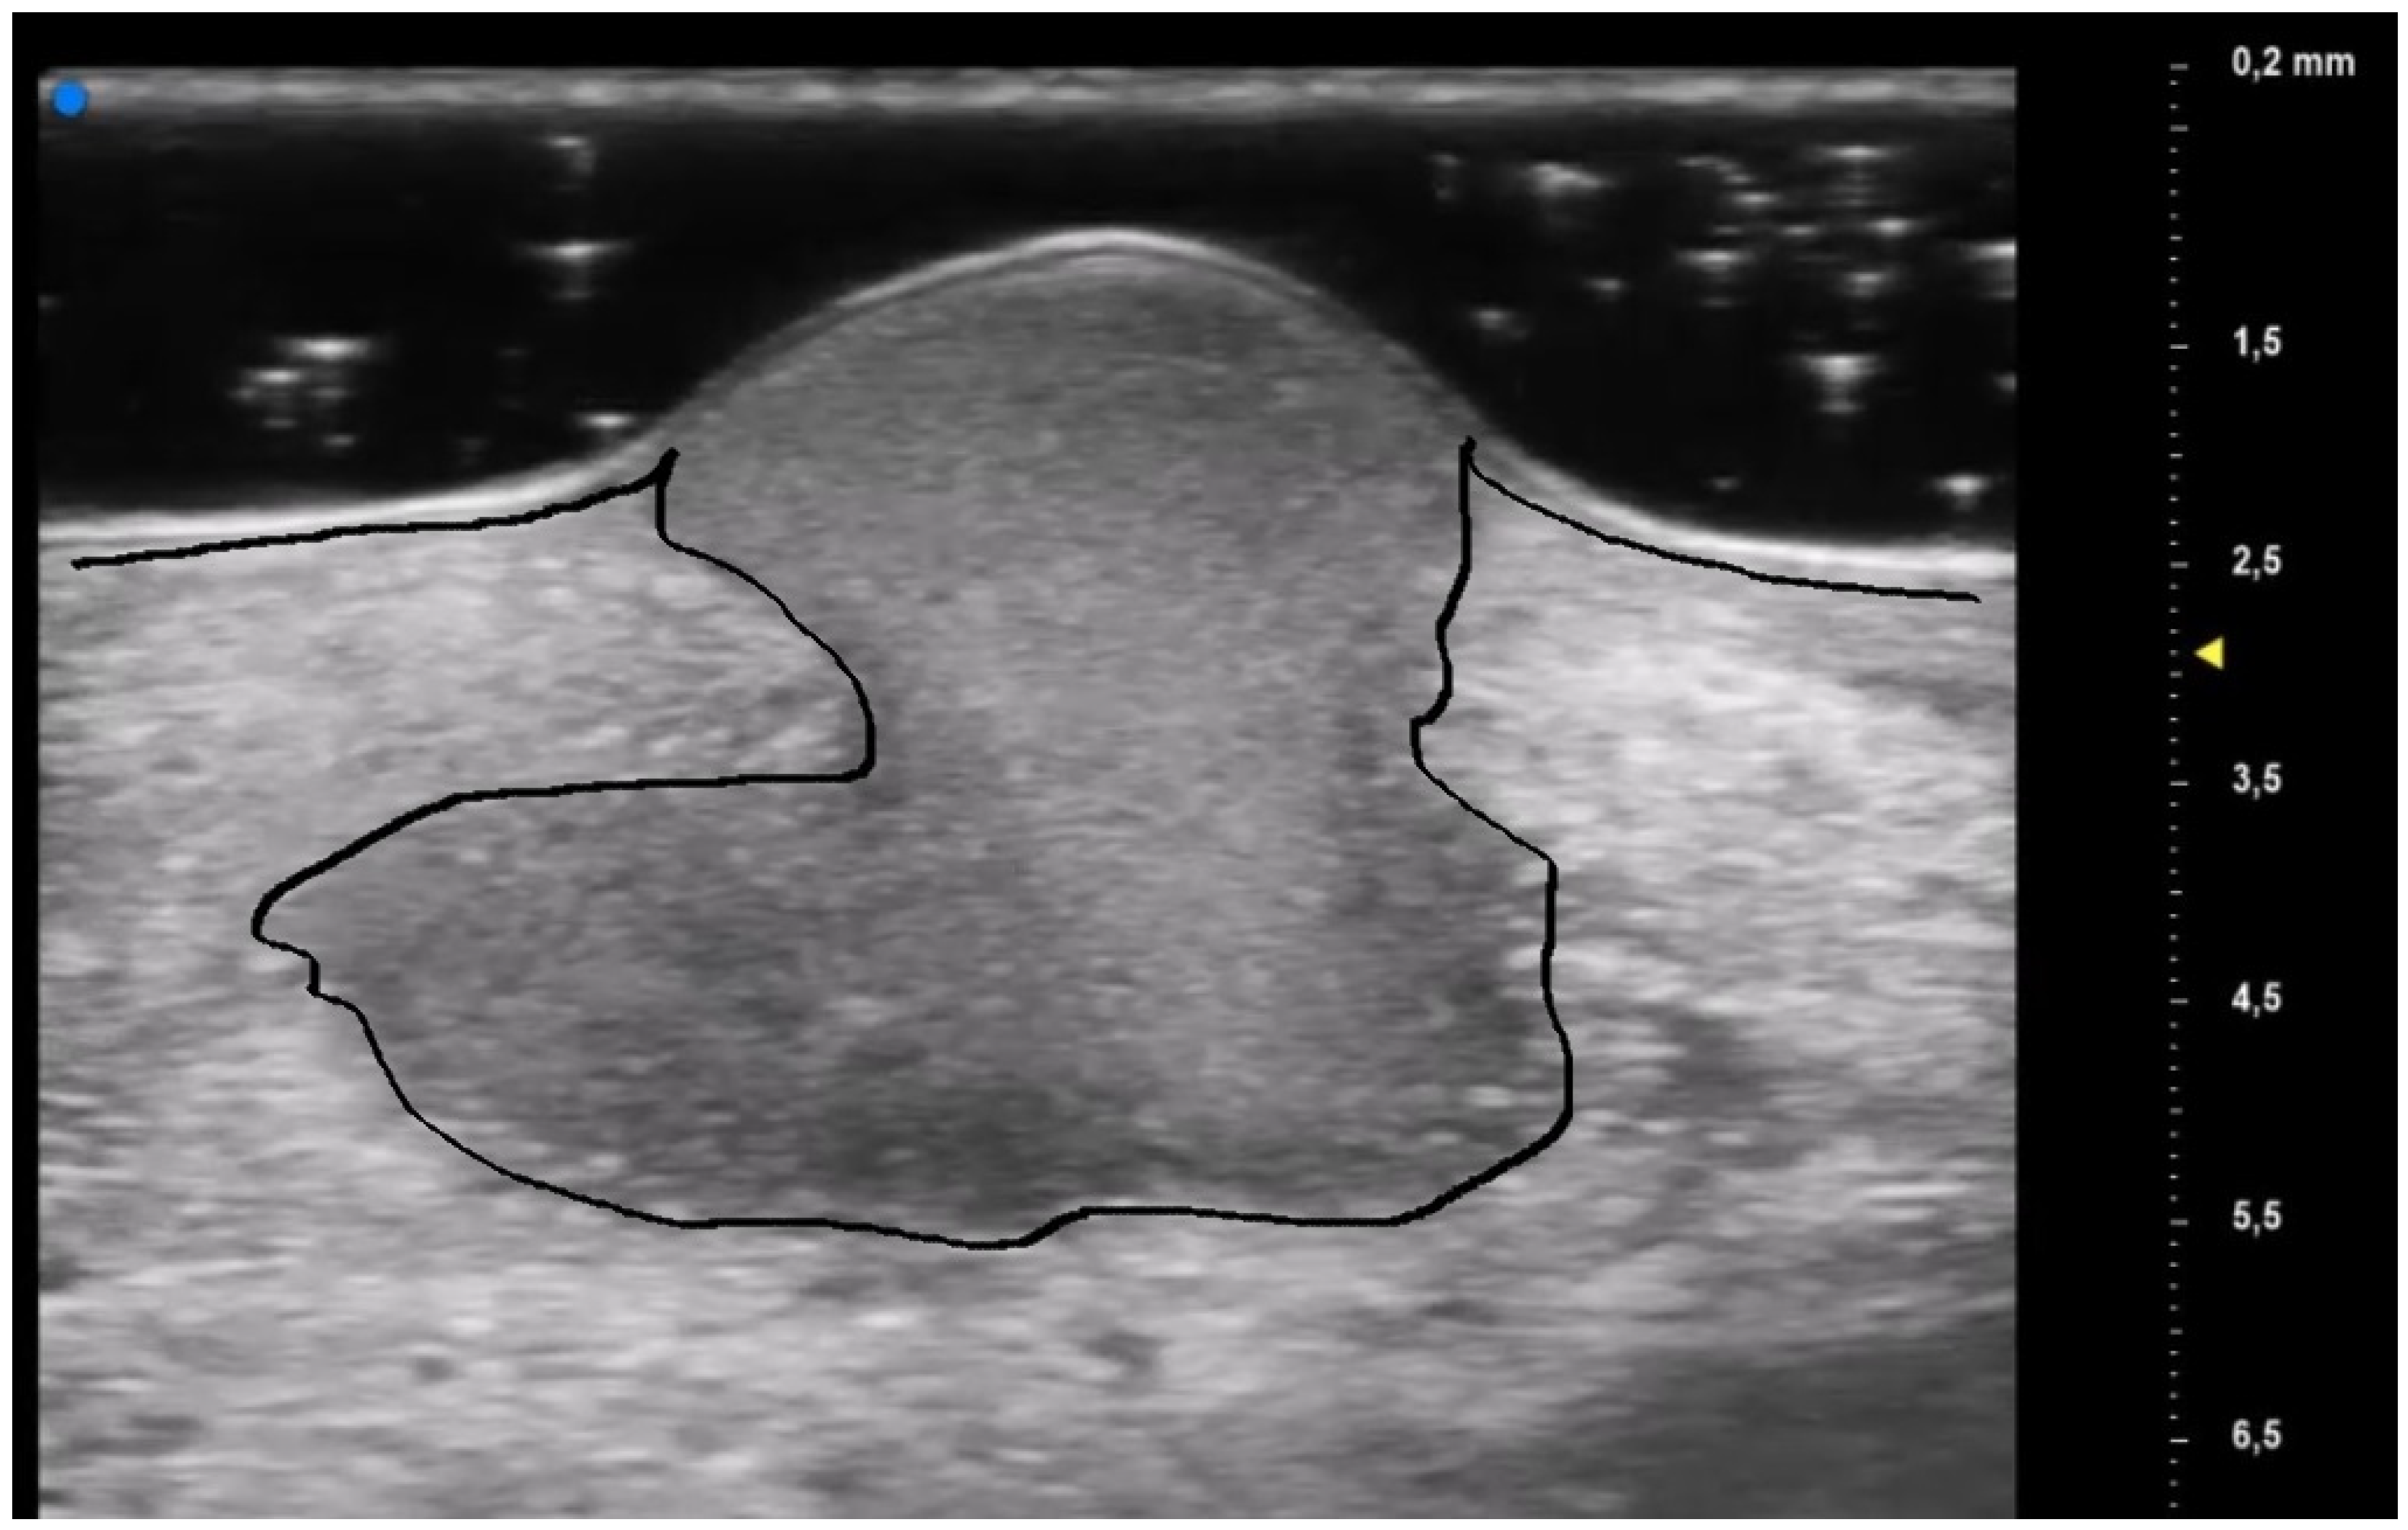

The results obtained by our investigation revealed some UHFUS differences between the inflammatory and non-inflammatory phases. At T0, oval hyperechoic structures, that statistically significantly decreased in T1, were identified in the papillary and reticular dermis (p-value < 0.05) (Figure 4 and Figure 5).

These US findings spared the epidermis and were well demarcated from the surrounding dermis, thus suggesting a hypothesis of “dermal destruction” that we called “tsunami sign” because of the presence of a US image resembling a wave breaking towards the center of the lesion (Figure 6). In T0, hyperechoic oval structures were mainly located at the level of the lesion edges, near V-shaped and U-shaped blood vessels, where the inflammatory response presented a higher activity. Particularly, in T0 an increased expression of U-shaped vessels compared to V-shaped vessels was detectable. In contrast, T1 was characterized by a more uniform vascularization with a significant reduction in U-shaped vessels (p-value < 0.05). These UHFUS findings could be explained by the increased dermal oedema in T0, which resulted in surrounding connective tissue compression and morphological blood vessels changes.

The UHFUS characteristics found in T0 decreased in number and density in T1, but did not disappear. This result could be explained by two theories. First, the permanence of some UHFUS features could be suggestive of a new potential inflammatory flair, thus justifying the need for immunomodulatory maintenance therapy even in the non-inflammatory phase. In addition, the persistence of oval formations/micro-abscesses and V-shaped vessels in the non-inflammatory phase promoted the hypothesis that these UHFUS patterns were pathognomonic signs of PG.

Moreover, the presence of similar UHFUS findings between the pustular and ulcerative phenotypes in T0, suggested the idea, not yet confirmed in the literature, that the pustular phenotype was an early stage of the ulcerative one, in agreement with the assumption of Powell et al. this hypothesis could be supported by our population’s anamnestic data that reveal a clinical onset with confluent or non-confluent pustules in 5 patients. (Figure 7) [12].

UHFUS examination showed the presence of a hair track within the oval hyperechoic structures in T0 and their disappearance in T1 (p-value < 0.05). This finding, as well as the increased U-shaped and V-shaped vessels in T0, could also support the idea that the pilosebaceous unit could play a pivotal role in PG pathogenesis.

Figure 6. Early PG lesion: the purulent material (included by the black line) is well demarcated and undermined from the surrounding dermis giving a wave-like appearance, the so-called “tsunami sign”.

Figure 7. UHFUS PG features: early PG pustule with hair tract (A1-2-3); undermined purulent material with the “tsunami sign” formation (B1-2-3); PG evolution toward ulceration (C1-2-3); PG lesion during non-inflammatory phase (D1-2-3); healed PG lesion (E1-2).